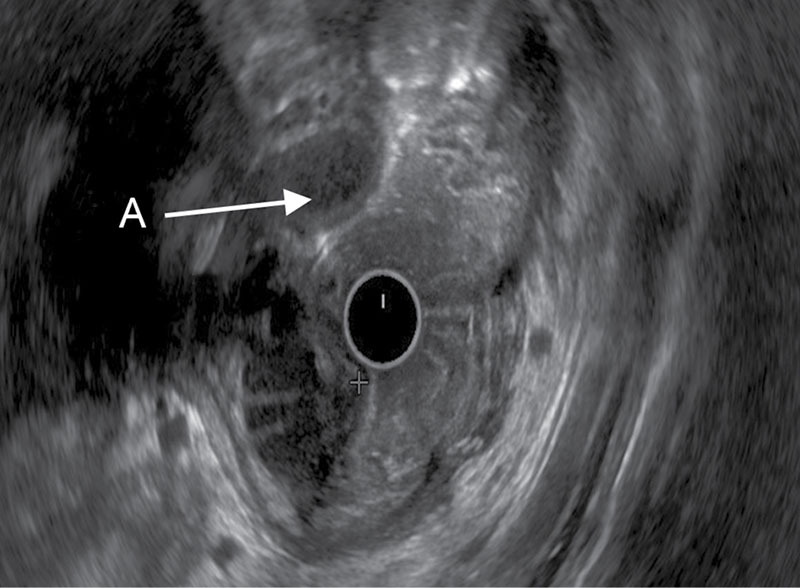

УЗИ диагностика кольцевидной поджелудочной железы: что важно знать